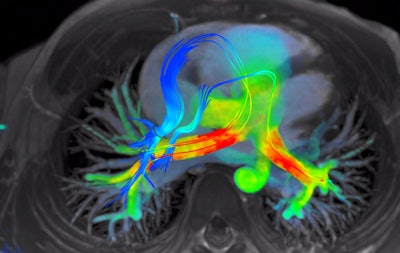

4D Flow depicts severe regurgitation on right-ventricular three-chamber view. Image courtesy of Arterys."That can replace a whole slew of conventional [MR] sequences that could take an hour to acquire," said John Axerio-Cilies, Arterys' co-founder and chief technology officer.

4D Flow software for cardiac MRI shows streamlines of shunted pulmonary venous flow back out to each pulmonary artery. Image courtesy of Arterys.Accomplishing the company's vision of making 4D Flow a clinical product required the use of cloud infrastructure, as it's not feasible to deliver the required computing power for the software to every local institution, said John Axerio-Cilies, Arterys' co-founder and chief technology officer. The company's platform -- called Arterys Cloud -- is the engine that supports widespread adoption of 4D Flow.